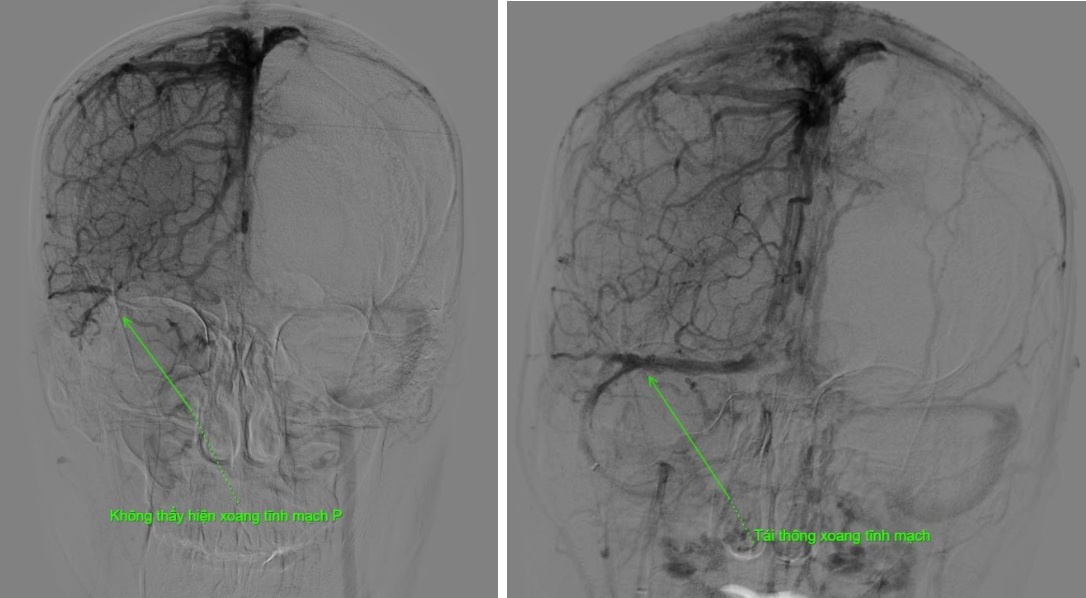

Hình ảnh phim chụp trước và sau can thiệp cho thấy rõ mức độ tắc nghẽn và hiệu quả tái thông sau thủ thuật.

Kết quả phim chụp cho thấy bệnh nhân bị tắc gần như toàn bộ hệ thống tĩnh mạch dẫn lưu não, bao gồm xoang dọc trên, xoang ngang, xoang sigma và đoạn đầu xoang tĩnh mạch cảnh trong phải.